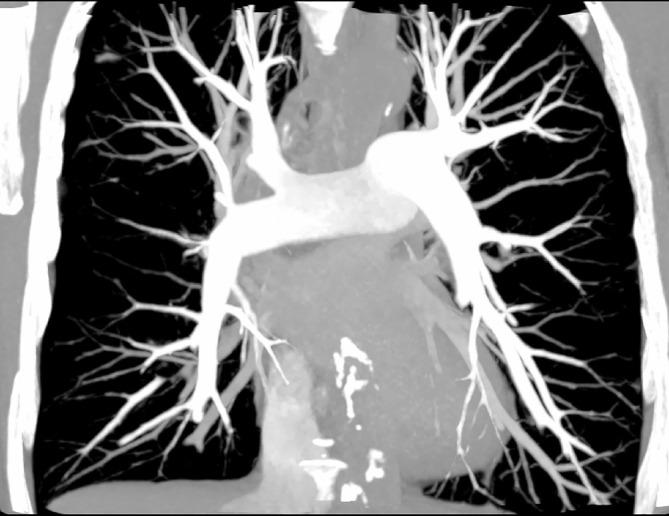

高螺距技术在 CT 肺动脉造影中降低对比剂剂量。

Minimizing contrast media dose in CT pulmonary angiography with high-pitch technique.

To perform CT pulmonary angiography (CTPA) using a minimal amount of iodinated contrast media.

47 patients (25 females) with mean age 69 years (range 41-82 years) referred for contrast-enhanced chest CT were prospectively included in this Phase IV clinical drug trial. All participants underwent a study specific CTPA in addition to the chest CT. The participants received 80 mg I/kg body weight Iohexol contrast media using a preparatory saline bolus, a dual flow contrast/saline bolus and a saline flush, and a scanner protocol with 80 kVp dual source high-pitch mode. Three readers independently assessed the image quality on the 3-point scale non-diagnostic, adequate or good-excellent image quality. Additionally, the pulmonary arterial contrast opacification was measured.

On average, the patients received 16.8 ml Iohexol 350 mg I/mL (range 12-20 ml). Mean patient weight was 71 kg (range 50-85 kg). Identically for all readers, pulmonary embolism (PE) was detected in 1/47 participants. The median number of examinations visually scored concerning pulmonary embolism as good-excellent was 47/47 (range 44-47); adequate 0/47 (0-3) and non-diagnostic 0/47 (range 0-0). The proportion adequate or better examinations was for all readers 47/47, 100% [95% confidence interval 92-100%]. The mean attenuation ± standard deviation in the pulmonary trunk was 325 ± 72 Hounsfield unit (range 165-531 Hounsfield unit).

Diagnostic CTPA with 17 ml contrast media is possible in non-obese patients using low kVp, high pitch and carefully designed contrast media administration.

By combining several procedures in a CTPA protocol, the contrast media dose can be minimized.